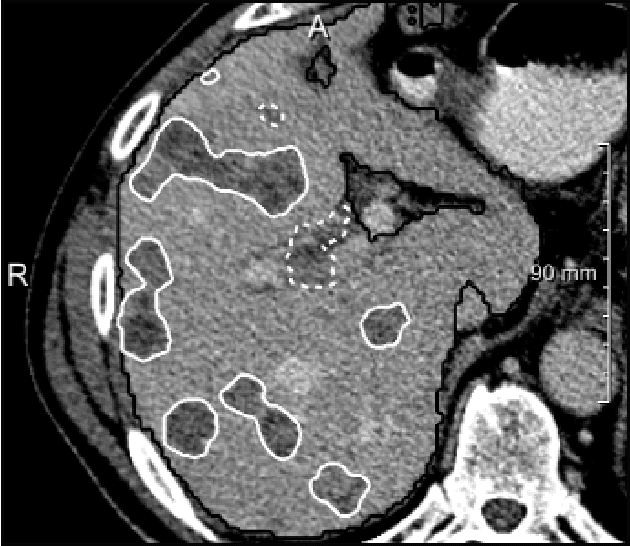

Abstract:In this work, we report the set-up and results of the Liver Tumor Segmentation Benchmark (LITS) organized in conjunction with the IEEE International Symposium on Biomedical Imaging (ISBI) 2016 and International Conference On Medical Image Computing Computer Assisted Intervention (MICCAI) 2017. Twenty four valid state-of-the-art liver and liver tumor segmentation algorithms were applied to a set of 131 computed tomography (CT) volumes with different types of tumor contrast levels (hyper-/hypo-intense), abnormalities in tissues (metastasectomie) size and varying amount of lesions. The submitted algorithms have been tested on 70 undisclosed volumes. The dataset is created in collaboration with seven hospitals and research institutions and manually reviewed by independent three radiologists. We found that not a single algorithm performed best for liver and tumors. The best liver segmentation algorithm achieved a Dice score of 0.96(MICCAI) whereas for tumor segmentation the best algorithm evaluated at 0.67(ISBI) and 0.70(MICCAI). The LITS image data and manual annotations continue to be publicly available through an online evaluation system as an ongoing benchmarking resource.

Abstract:We present a fully automatic method employing convolutional neural networks based on the 2D U-net architecture and random forest classifier to solve the automatic liver lesion segmentation problem of the ISBI 2017 Liver Tumor Segmentation Challenge (LiTS). In order to constrain the ROI in which the tumors could be located, a liver segmentation is performed first. For the organ segmentation, an ensemble of convolutional networks is trained to segment a liver using a set of 179 liver CT datasets from liver surgery planning. Inside of the liver ROI a neural network, trained using 127 challenge training datasets, identifies tumor candidates, which are subsequently filtered with a random forest classifier yielding the final tumor segmentation. The evaluation on the 70 challenge test cases resulted in a mean Dice coefficient of 0.65, ranking our method in the second place.